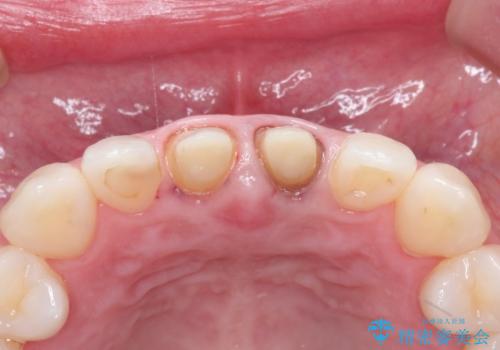

- 10年前ほどに前歯に装着されたセラミックの根元の方が黒くなってきたのが気になるとのことで来院されました。

上顎の前歯の歯茎が下がり、ご自身の歯が露出している状態でした。

金属の土台をファイバーコアに交換後、オールセラミッククラウンを装着する計画としました。